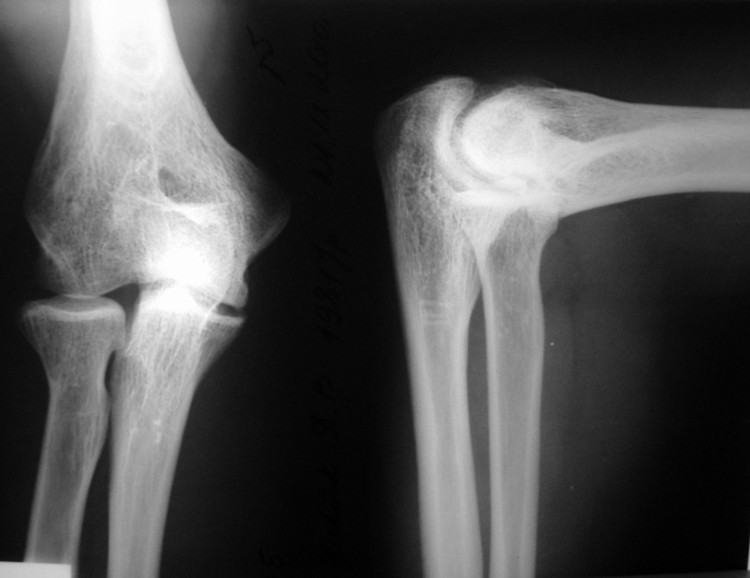

Уважаемые коллеги! Выскажите, пожалуйста, свое мнение по данному случаю. Пациент очень решительно настроен прооперироваться с целью улучшения функции. Мужчина, 29 лет. В 15 лет - спортивная травма, закрытый чрезмыщелковый перелом правой плечевой кости со смещением. Лечился консервативно. В настоящее время предъявляет жалобы на ограничение сгибания, повышенную утомляемость. Объективно: сгибание до 100 гр., разгибание до 170. Неврологических и циркуляторных расстройств нет. Вопрос: возможность хирургического лечения с целью улучшения функции (вид, детали, прогноз)?

Male, 29 y.o. In age of 15 years he had sport trauma – close transcondylar fracture of the humerus. He had cast fixation and some rehabilitation after it.

Now: complaints for limitation of the flexion, fast weariness.

Flexion: 100 degree, extension – 170. There are no neurological and vascular disorders.

Question: possible surgical treatment for better function of the elbow (opinion, type of surgery, details, prognosis)?